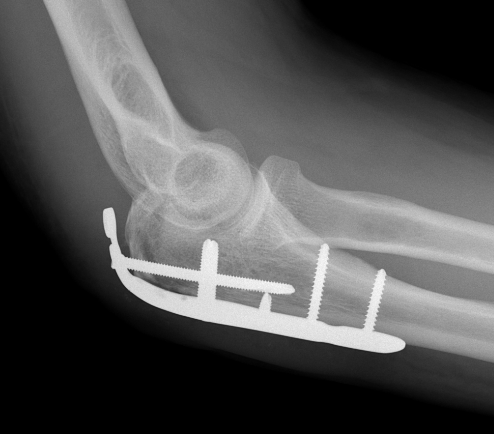

ORIF with olecranon plate

Indication

Fracture distal to center of rotation of elbow / trochlea

Technique

Lateral decubitus with tourniquet

- curvilinear incision to avoid prominence of olecranon

- identify and protect ulna nerve

- reduce fracture with arm in extension

- ensure articular congruity

- use anatomical precontoured plate

- may want to split distal triceps to reduce proximal plate prominence